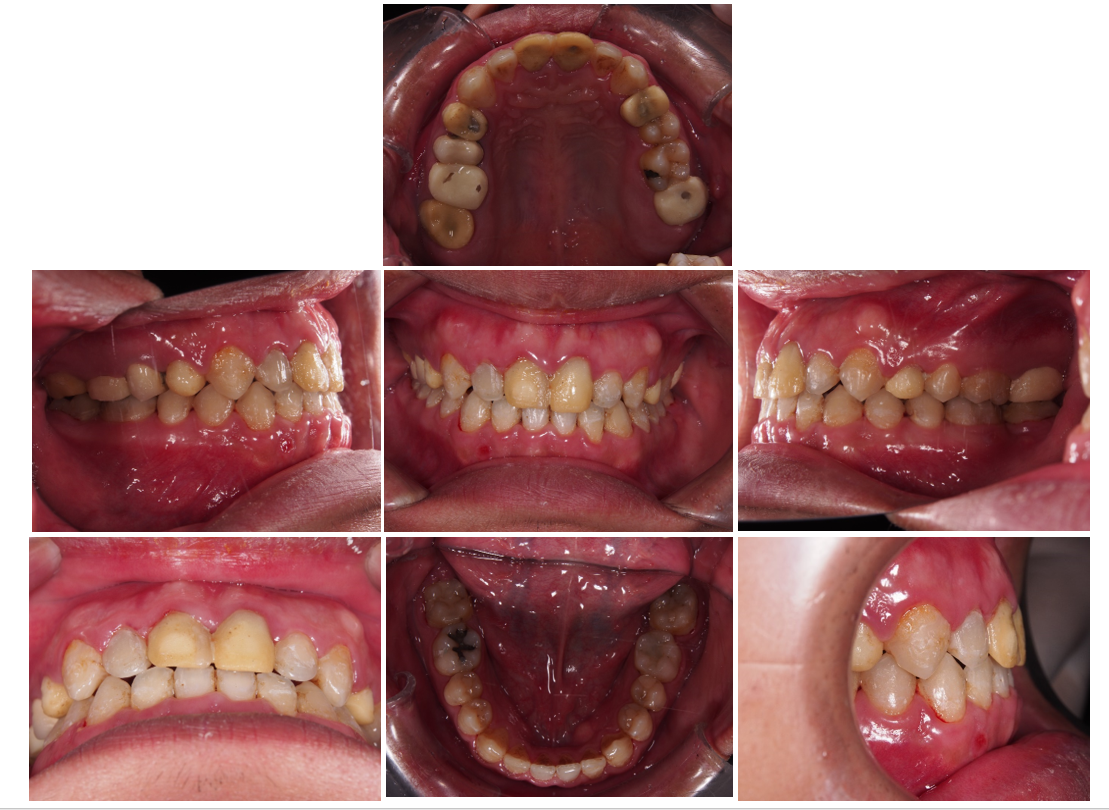

治療前 :前牙錯咬,上下排齒列不整,蛀洞大,左下缺牙空間大。

治療後 :左下缺牙空間靠矯正成功關起來,齒列整齊,前牙調整至正確咬合位置。

下排缺牙位置可以靠矯正關起來,省了一顆植牙的錢。但要矯正之前須要先處理好牙周,假牙問題。 讓我們矯正+牙周+假牙醫師相互配合吧!!!

臨時假牙更換完畢,再由矯正專科 穆慧英醫師 接手把牙齒排列完成。